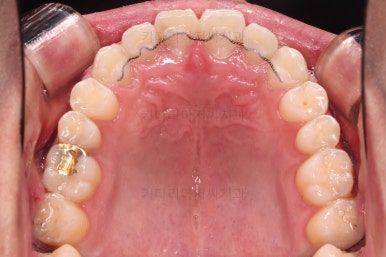

우선 치열이 가지런해졌으면 우리의 목표인 치열을 통째로 뒤로 미는 과정을 진행합니다.

잇몸뼈에 미니스크류라고 하는 아주 작은 임플란트를 식립하고요.

미니스크류를 이용해서 뒤로 당겨주게 됩니다.

어느 정도 아랫니가 뒤로 와서 위아래의 교합이 맞춰졌다 생각들면 윗니도 함께 뒤로 당겨줍니다.

그래야 뻗쳐있던 앞니의 각도도 좋아지고, 코-입술 각도(비순각)도 좋아지기 때문이죠.